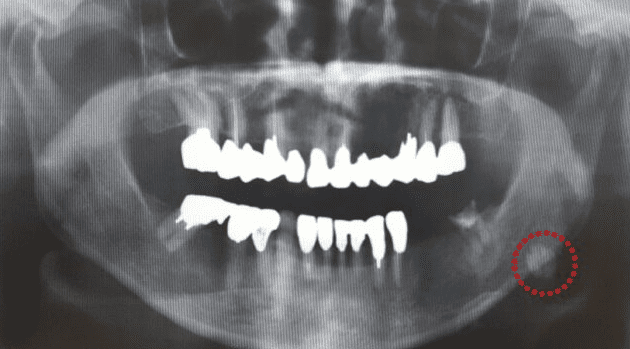

2. 影像學診斷

除了直接的身體檢查外,影像學檢查提供了更準確的輔助診斷方式,特別是在判斷唾液腺結石的大小、位置和影響範圍方面。

超音波檢查(Ultrasound, US): 超音波因其操作方便、無輻射且適合用於唾液腺,是第一線的成像選擇。超音波可以清晰顯影位於腮腺或頜下腺的結石,並幫助醫生確認結石的大小及其是否阻塞導管。此外,這種診斷方式對於動態唾液流的評估也非常實用,能夠進一步區分功能異常和實質阻塞的原因。

電腦斷層(Computed Tomography, CT): 若超音波不足以清晰診斷或臨床懷疑結石較深藏在腺體組織中,醫生可能採用 CT 篩檢。與其他成像技術相比,CT 可提供更多結構性的三維資訊,並在結石成分具有較高密度特性的時候有較佳的辨識效果,因此是對高密度的磷酸鹽和碳氫磷石灰結石的理想選擇。